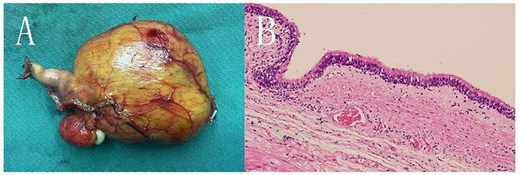

During surgery, a lump was identified behind the tail of the pancreatic body, with no apparent adhesion or invasion of the surrounding area. The pancreatic tail was completely freed and suspended along with the splenic artery and vein, revealing that the mass originated from the lesser curvature of the stomach (Fig. 2). After fully dissociating the mass, the gastric tissue was separated from it along the lesser curvature, and the mass was completely removed from the surface of the left renal vein. The mass, visible to the naked eye, measured approximately 5 × 6 cm (Fig. 3), and yellow viscous content was observed upon incision. Postoperative pathological examination revealed a retroperitoneal mass. The fibrous cyst wall tissue was lined with ciliated columnar epithelium, with numerous foam cells and lymphocyte infiltration, suggesting a diagnosis of bronchogenic cyst (Fig. 3). The postoperative diagnosis included gastric bronchogenic cyst, gallbladder stones with chronic cholecystitis, and coronary atherosclerotic heart disease. The patient received postoperative symptomatic treatment, including antiinfection therapy and fluid replacement. A follow-up abdominal CT scan six days after surgery showed no obvious residual cysts (Fig. 1C), and the patient was discharged.

A: The cyst seen with the naked eye, displaying a clear boundary. B: HE staining under a light microscope (10 × 20 magnification) showing the cyst wall tissue, with ciliated columnar epithelium, foam cells, and lymphocytes visible.